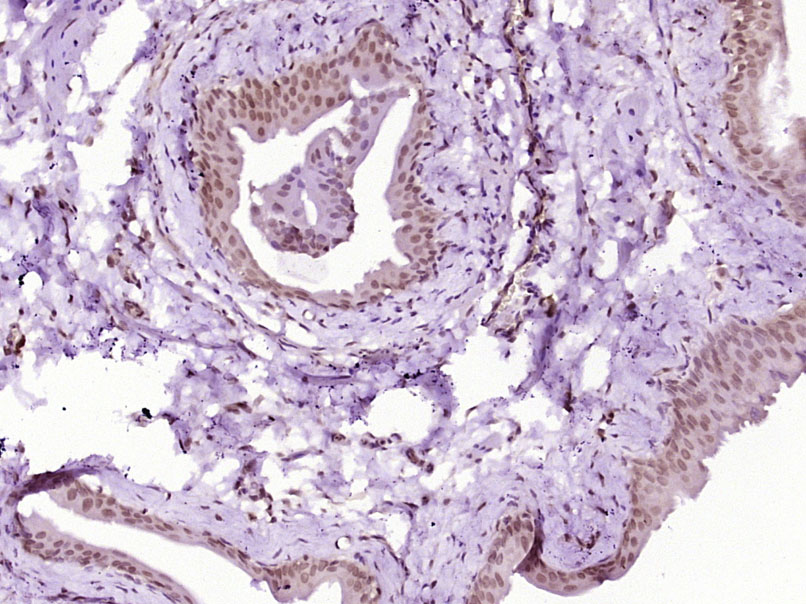

Paraformaldehyde-fixed, paraffin embedded (rat lymphoid); Antigen retrieval by boiling in sodium citrate buffer (pH6.0) for 15min; Block endogenous peroxidase by 3% hydrogen peroxide for 20 minutes; Blocking buffer (normal goat serum) at 37°C for 30min; Antibody incubation with (Phospho-NFKB p65 (Ser468)) Polyclonal Antibody, Unconjugated (bs-3485R) at 1:200 overnight at 4°C, followed by operating according to SP Kit(Rabbit) (sp-0023) instructionsand DAB staining.